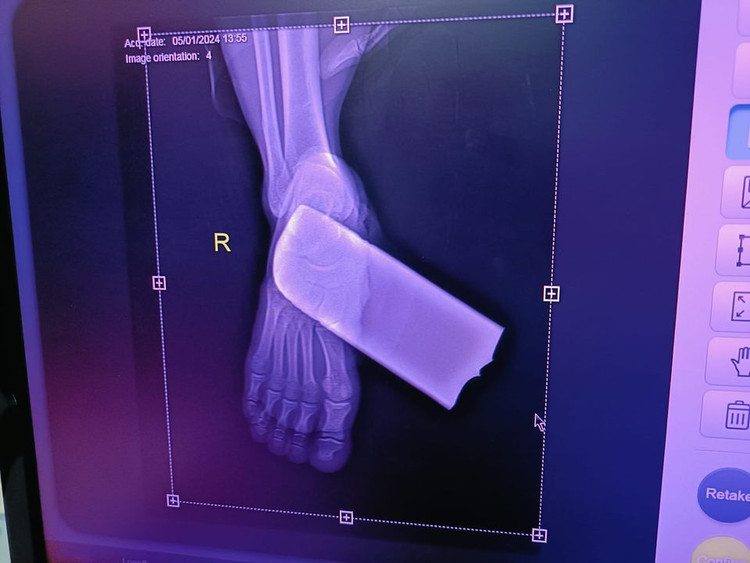

BS.CKI. Vương Văn Côn, Khoa Chấn thương chỉnh hình, Bệnh viện đa khoa tỉnh Tuyên Quang (Trưởng kíp mổ cho bệnh nhân H.) cho biết: Bệnh nhân bị lưỡi máy cắt cỏ gãy bắn găm vào bàn chân phải gây tổn thương đứt cơ gan bàn chân và mạch máu.

| Bệnh nhân bị lưỡi máy cắt cỏ gãy bắn găm vào bàn chân phải gây tổn thương đứt cơ gan bàn chân và mạch máu |